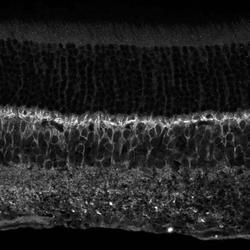

NBP1-98572 IHC

Full details

Method:

Other validation